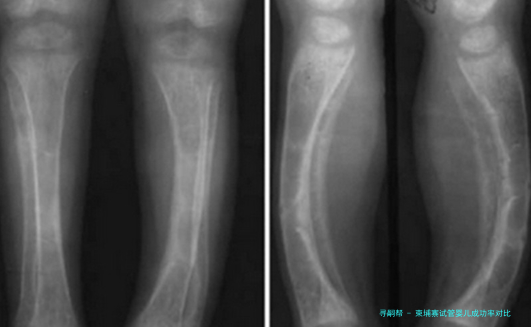

柬埔寨试管婴儿成功率相比

目前第三代试管婴儿技术成功率比较高的国家即是美国,可达百分之八十五左右,但是其费用同样是比较高的;柬埔寨试管婴儿成功率大概是60%左右,相比较美国而已,是要低一些的。